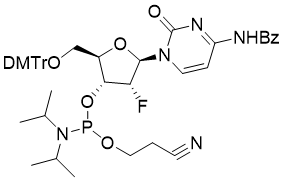

馬鞍山致研生物醫(yī)藥科技有限公司成立于馬鞍山市鄭浦港新區(qū)現(xiàn)代產(chǎn)業(yè)園。公司專(zhuān)注于生物小分子、醫(yī)藥中間體相關(guān)產(chǎn)品的研發(fā)和生產(chǎn),產(chǎn)品主要包括DNA亞磷酰胺單體、RNA亞磷酰胺單體、特殊單體以及按照客戶(hù)要求定制的RNA和DNA,并且公司提供定制合成等方面的研究服...

馬鞍山致研生物醫(yī)藥科技有限公司成立于馬鞍山市鄭浦港新區(qū)現(xiàn)代產(chǎn)業(yè)園。公司專(zhuān)注于生物小分子、醫(yī)藥中間體相關(guān)產(chǎn)品的研發(fā)和生產(chǎn),產(chǎn)品主要包括DNA亞磷酰胺單體、RNA亞磷酰胺單體、特殊單體以及按照客戶(hù)要求定制的RNA和DNA,并且公司提供定制合成等方面的研究服...